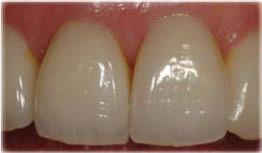

El innovador Disilicato de Litio (LS2) del sistema de cerámica vítrea IPS e.max CAD no solo ofece una altísima estética sino que también es de 2,5 a 3 veces más resistente 360 MPa que el resto de cerámicas de vidrio. Por ello, este material cubre todos los requerimientos estéticos y también representa una alternativa eficiente a las restauraciones unitarias de Zr02 (Zirconio).

El innovador Disilicato de Litio (LS2) del sistema de cerámica vítrea IPS e.max CAD no solo ofrece una altísima estética sino que también es de 2,5 a 3 veces más resistente 360 MPa que el resto de cerámicas de vidrio. Por ello, este material cubre todos los requerimientos estéticos y también representa una alternativa eficiente a las restauraciones unitarias de ZrO2. (Zirconio)

IPS e.max está avalado por la experiencia clínica que ha demostrado durante años, tanto en estética como en resistencia. La amplitud de elección del material, según el caso, en conjunción con la técnica empleada en nuestro laboratorio dotarán a los trabajos de la mayor estética para sus pacientes.